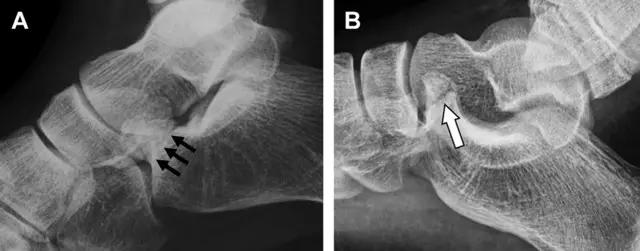

20 跟骨前突骨折

呈 Y 形的分歧韧带附着于跟骨前突上,是维持踝关节跖屈和背屈稳定性的重要结构。跟骨前突骨折常发生于足跖屈内旋、分歧韧带被牵拉时,或者足背屈外旋、骰骨和距骨挤压前突时。而这些骨折在初次 X 线检查时常常被漏诊掉。踝部侧位片诊断这些骨折最佳,准确诊断的关键点在于,必须仔细查看是否存在骨皮质中断(图 6)。如果侧位片可疑,建议加做斜位片协助诊断。

图 6 跟骨前突骨折。A 侧位片示跟骨前突骨折(箭头),与舟骨的重叠使骨折显示模糊;B 另一位患者的侧位片示内翻损伤所致的骨折(箭头),这种损伤机制引起小块的骨折

21趾短伸肌跟骨撕脱性骨折

另一种重要的跟骨撕脱性骨折,于足内翻时发生在趾短伸肌的起点处。观察来自跟骨背外侧的、不同大小的骨折块,前后位 X 片最适合不过了(图 7)。

图 7 溜冰受伤的患者,趾短伸肌跟骨撕脱性骨折。正位片示 2 个骨折块(箭头)来源于跟骨前外侧、趾短伸肌的起点处。踝关节外侧远端是否存在软组织水肿是一个重点观察点